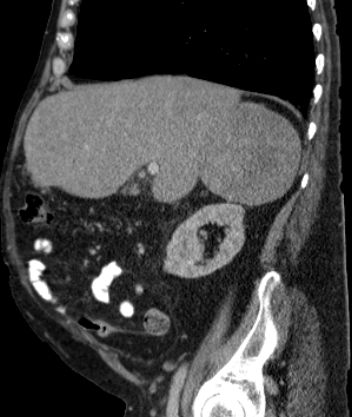

Phaeochromozytom Tumoren des Nebennierenmarks

Nebennieren - Rinden - Tumoren

Diagnostik